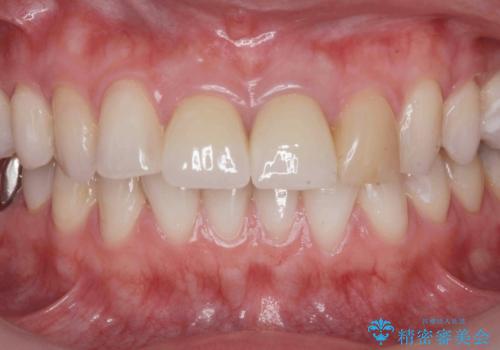

- 24.2万円(仮歯・ジルコニアクラウン×2)費用は治療当時の料金となります

前歯の見た目が改善したことで長年の悩みが解決できた。と治療内容に満足いただくことができました。